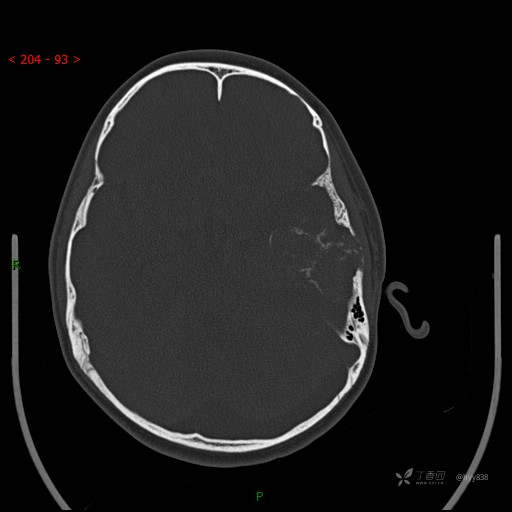

“典藏”病例分享。10岁儿童,头痛头晕一周余,CT、MRI 都有---结果公布~

简要病史:患者于一周前无明显诱因开始出现头痛头晕,无恶心呕吐,无肢体抽搐,无寒颤高热,无腹胀腹泻,无视力下降及视野缺损,上述症状休息后可稍缓解,未引起重视。 2天前患者头痛头晕不适加重,伴有恶心感,无呕吐,遂到当地人民医院行头颅CT检查示:左侧颞部占位性病变,今日家属为求进一步治疗,来我院门诊求治。门诊拟“左侧颞部占位性病变”收入我科。 患病以来,患者精神、饮食、睡眠尚欠佳,大小便如常,体力体重无明显变化。

临床诊断:左侧颞部占位

颅脑CT扫描